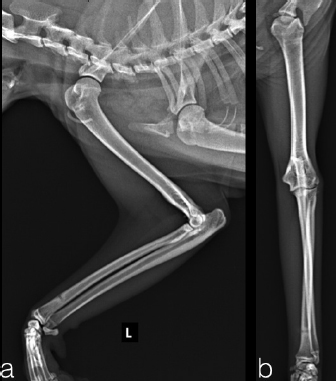

Two, spayed, Domestic Shorthaired cats with an age of 1.5 years (case 1) and 6 years (case 2) were referred to the author’s clinic for the non-weight bearing left forelimb lameness after a suspected trauma. Physical examination, of both cats, revealed moderately swollen and painful left elbow, with abnormal posture characterized by extended rotation of antebrachium and supination of the paw. Orthogonal radiographs of forelimbs demonstrated a complete caudal elbow luxation (Fig. 1). The radius and ulna were caudally and proximally displaced in relation to the humerus; furthermore, in case 1, a small avulsion bone fragment (2 mm diameter) closed to the lateral aspect of the humeral condyle was presented. No other abnormality was identified during the physical and radiographic examinations. The cats were sedated by intramuscular administration of dexmedetomidine (Dexdomitor: Pfizer Italia Srl, Rome, Italy) (10 μg/kg) and methadone (Semfortan: Dechra Veterinary Products Srl, Turin Italy) (0.4 mg/kg). General anesthesia was induced with propofol (Proposure: Merial Italia Spa, Milan, Italy) (6 mg/kg) intravenously and, after oro-tracheal intubation, maintained with isoflurane (IsoFlo: Aesica Queenborough Limited, Kent, United Kingdom) and oxygen. Modified closed reduction technique was attempted in both cases. Distal traction of antebrachium with full extension of the elbow was initially achieved followed by simultaneously applying distal pressure on the olecranon and partial elbow flexion. Following successful reduction, the collateral ligaments integrity was indirectly assessed with the Campbell’s test (1971), with normal limits value around 110° of supination and 70° of pronation recorded in both patients. The joint stability and reduction were maintained with gentle manipulation. However, instability was present at 100° of elbow extension, while major stability was obtained at 40° of flexion. For this reason, the elbow was held at 40° of flexion and a simple transarticular external skeletal fixator type IIa was applied to maintain the stability of the joint. Due to the forced flexion position, which limited the biomechanics movement, the cats were not able to weight bearing in the postoperative period. Two full pins, smooth Kirschner wires 2.0 mm of diameterf were inserted in the proximal third of the diaphysis of the humerus and in the distal third of the radial diaphysis. Stainless steel connecting bars (Gènia. St. Hilaire de Chaléons, France) (3.0 mm) were positioned medially and laterally connecting with Maynard clamps (Gènia. St. Hilaire de Chaléons, France) to the full pins (Fig. 2). The avulsion bone fragment was not treated in case 1. The patients were discharged from the clinic 24 hours after surgery. Cage rest without any exercise was recommended for 2 weeks and meloxicam (Meloxoral: Fatro S.p.A., Ozzano Emilia, Italy) (0.05 mg/kg) was administrated for 7 days.

Fig. 1. Pre-operatively radiographs in lateral (a, c) and cranio-caudal (b, d) view. Case 1 (a–b); case 2 (c–d).